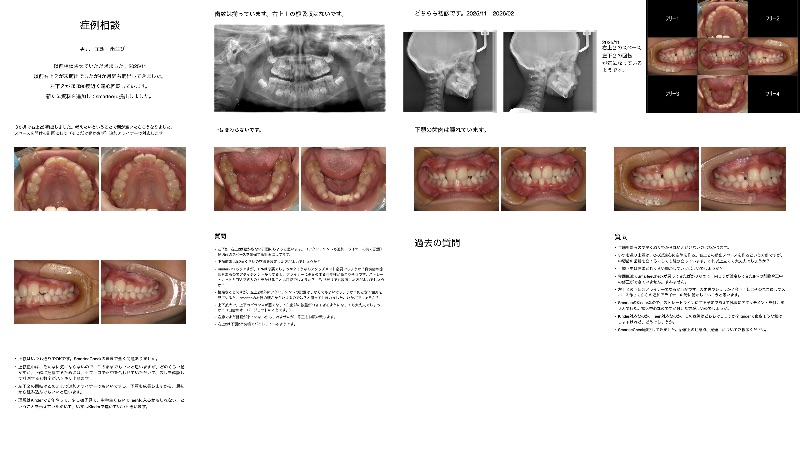

Q

Mさん、40代女性、主訴は「前歯を下の歯より前に、きれいに並べたい。にっこり笑った時に、真白な歯が綺麗に並んでいるのにあこがれている。」とのことでした。

前歯部だけでなく、臼歯部にも逆被蓋の部位がありますが、本人は機能的な問題は自覚なし。見た目が良くなれば良いそうです。

小学生のお嬢さんが骨格性の反対咬合を当院で治療中で、自分もやりたくなった。とのことでした。相談したいことは、

①外科を避けたカモフラージュ矯正は可能でしょうか?資料どりをする前は、口腔内を見て、上顎大臼歯の遠心移動と、下顎4番抜歯だけでいけるかな、MSEやってみるしかないのかな、と思っていたのですが、

パノラマより、上顎骨が薄く、とくに上顎の大臼歯は動かしたら抜けちゃうのでは?と心配です。

左上顎洞炎の疑いがあるので、まず耳鼻科を受診してもらおうと考えています。

CTでは、2023年に抜歯した左上智歯の抜歯窩が上顎洞と交通しており、左上犬歯の唇側に歯槽骨が見えませんでした。下顎前歯部の唇側皮質骨も薄かったです。

下顎大臼歯部だけはインプラントアンカーを打てる皮質骨の厚みがありました。

上顎骨が貧弱すぎて、外科矯正をする矯正歯科専門医にご紹介しても、迷惑だろうな、と思ってしまいました。②インビザラインとSmarteeだと、どちらが安全に治療できるでしょうか。ブラケット治療の方が優位な点等ありますか?

どちらも出すだけ出してみました。

ご指導のほど、よろしくお願いいたします。

矯正頑張るよりも、補綴のみで前歯をきれいに作る方が良いのかな、それも長持ちさせるためにはどうしたら良いのか、難しいなぁ、と考えています。 -